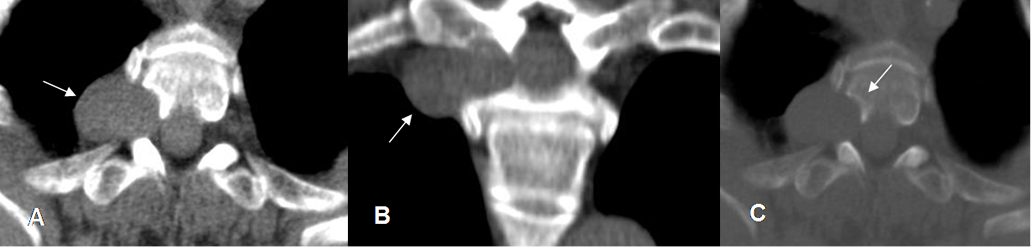

Fig 177. Signo de Target.

A y B: RM axial en T2. Neurofibromas en el nervio ulnar, con signo de Target. (Zona hipointensa central).